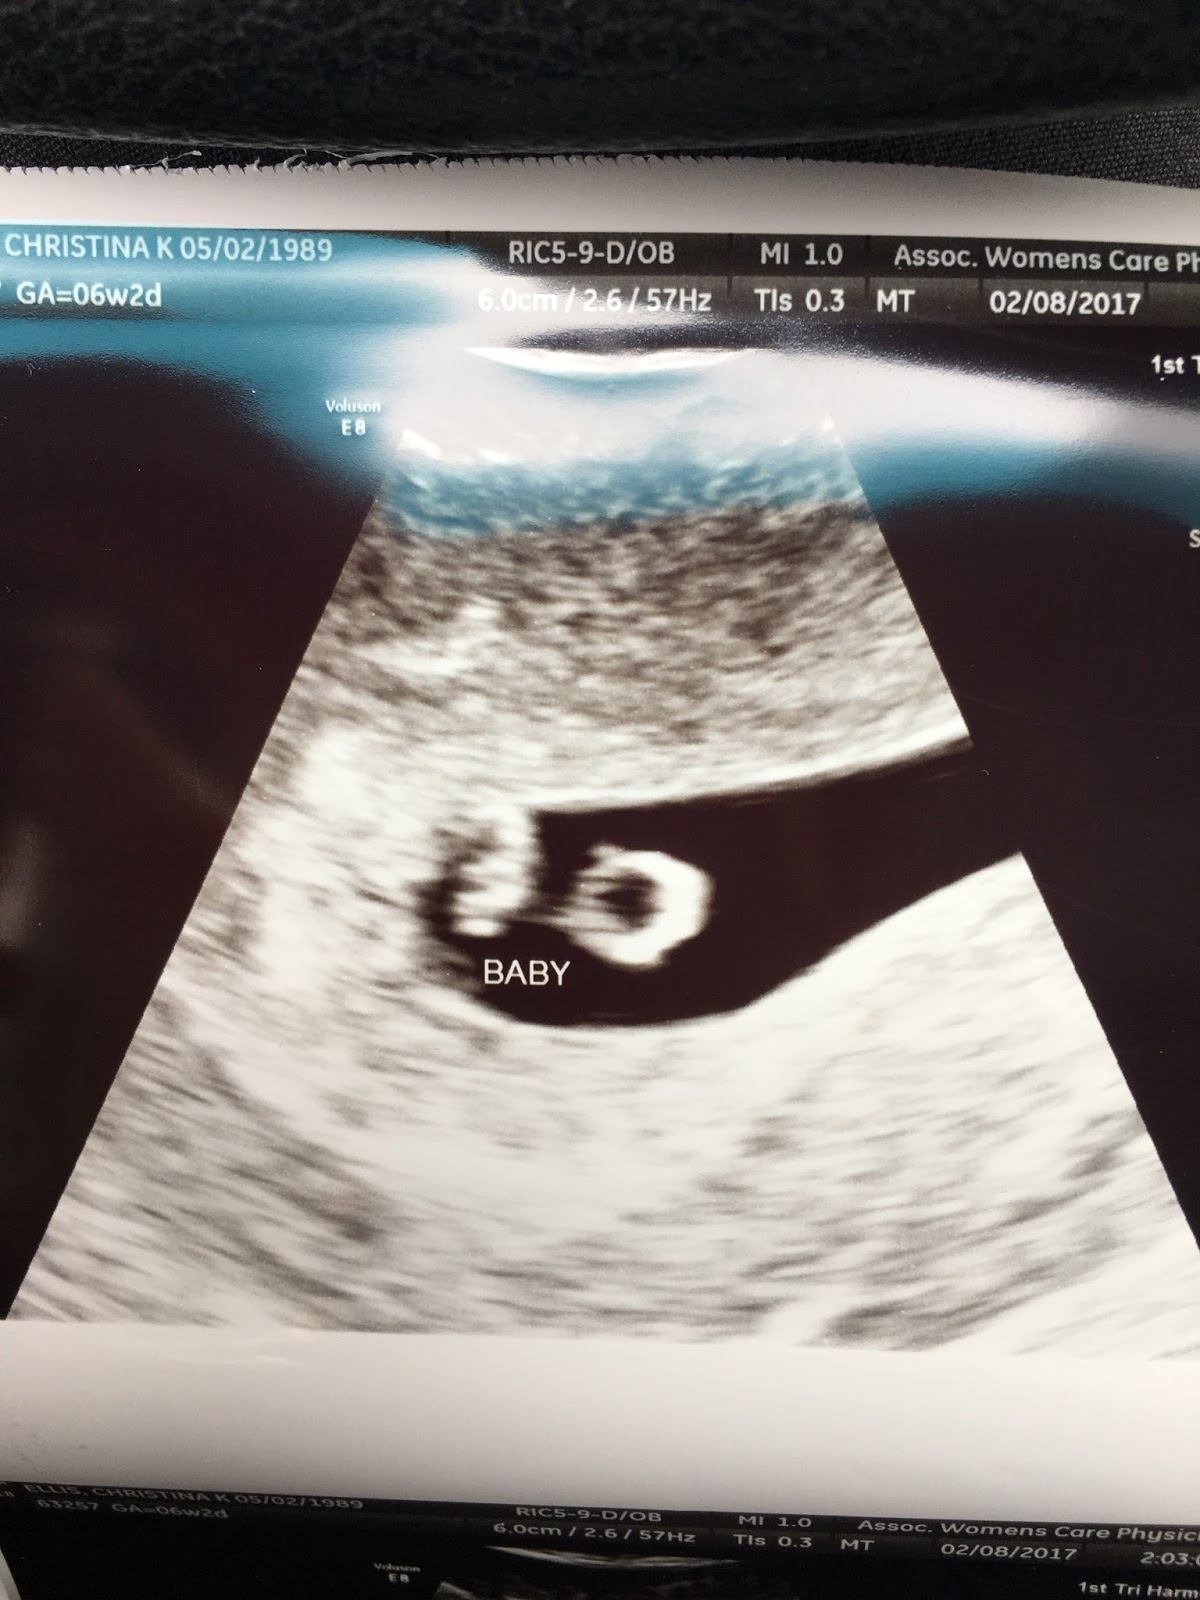

So, without further adieu, here is our little pumpkin who will grace us with their presence this fall.

I was called into the exam room by the same ultrasound technician who had helped diagnose both miscarriages... She remembered me and asked me how I was doing. I told her I was nervous and she was very positive. She told me the outcome was going to be good and that I shouldn't be worried. As I lay on the table looking at the screen, I see her skim past what I recognized as a gestational sac with something in it. I saw my baby. She then told me, "I'm going to do everything else first before we get to the big finish, okay?" So, I sat there anxiously watching her measure my ovaries and whatever else was in there of importance. Finally, my baby appears on the screen. It was there for only a second when she said, "And there's the baby with a nice strong heartbeat! Congratulations!" I started crying. I even told her I didn't expect to cry. To be honest, I didn't cry at my son's ultrasound. I guess at that point, I didn't even expect a miscarriage. I just expected everything to be fine. It was just such an amazing feeling after everything we went through last year to see our baby, heart beating away, measuring right on track. It was the cutest grain of rice I've ever seen. I can say that because Reilly didn't really look like a grain of rice at his first ultrasound. The picture we got of him was so small he just looked like a blob. It really was just such a magical moment. I got dressed and walked out of the room just looking at this picture of this little life we created. Overcome with emotion, I just wept. I don't know if people were worried or happy for me as I walked through the waiting room but I didn't care. Our baby is healthy and strong and I couldn't be happier!

(Baby is the grain of rice shaped thing to the left of the circle aka yolk sac)